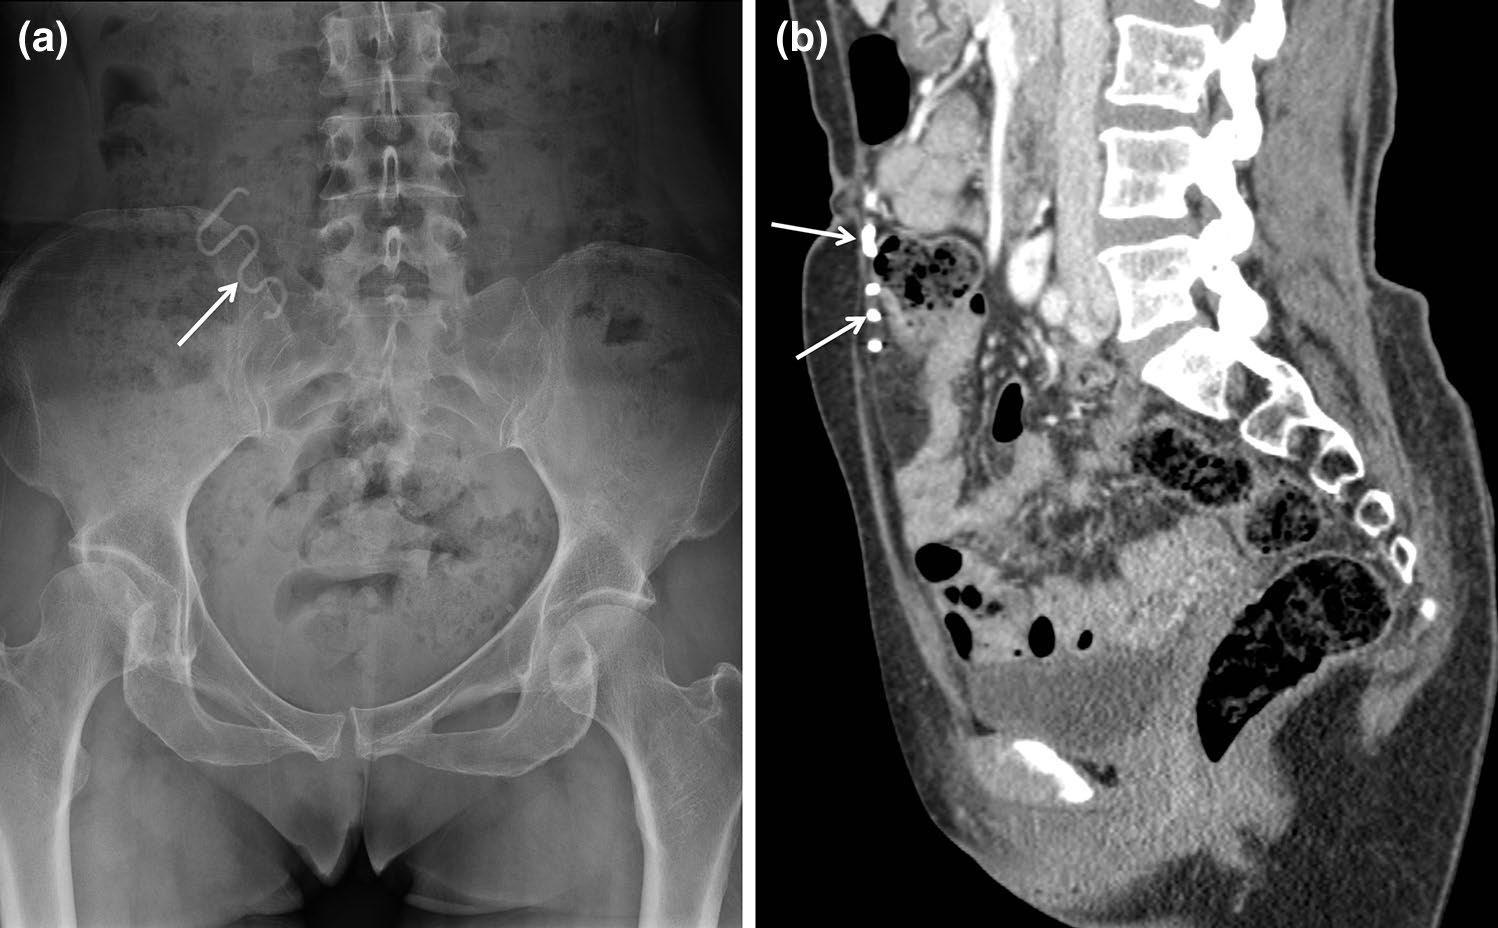

输尿管支架

输尿管支架通常用于治疗输尿管梗阻或瘘(图4)[7]。支架的近端和远端部分设计为J形或猪尾形,以防止从输尿管迁移。然而,由于蠕动作用,支架仍可能发生迁移(图5)[7]。